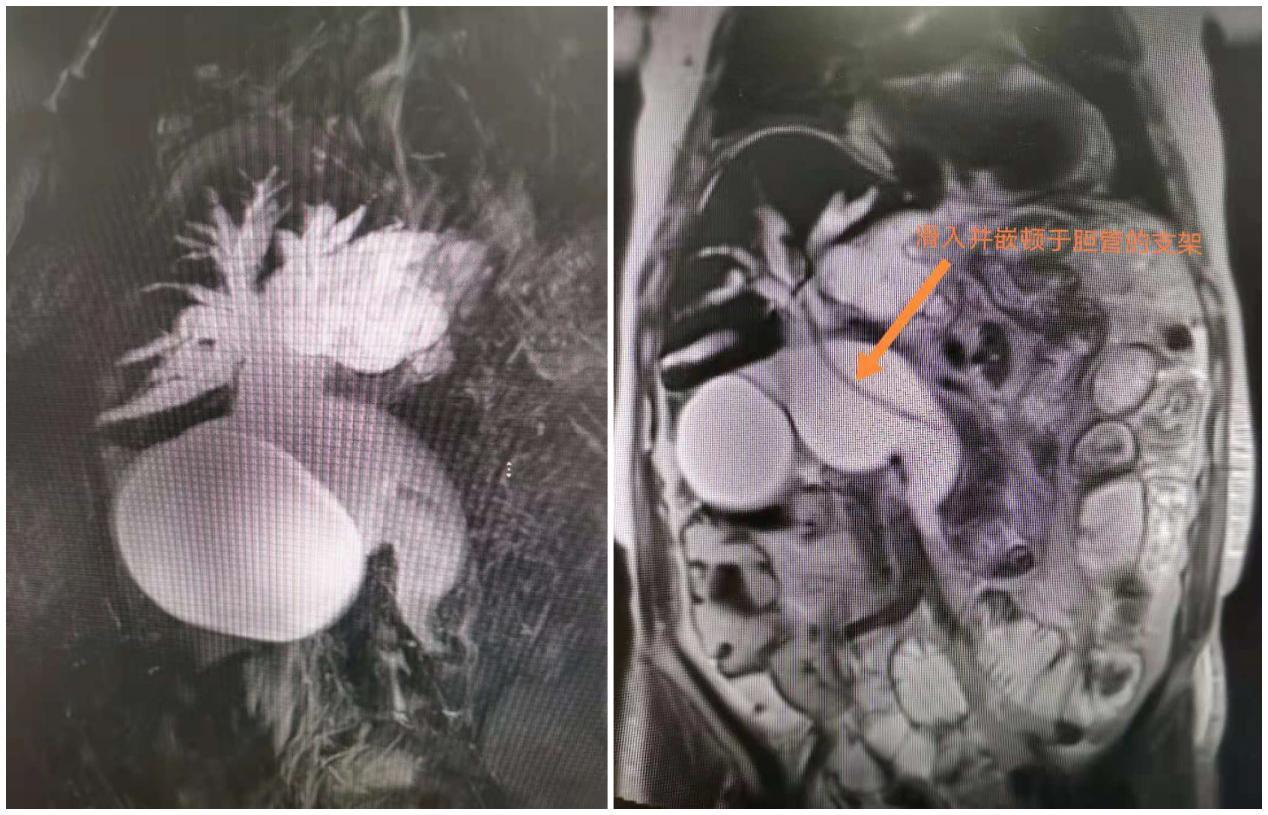

76岁的李奶奶来自江西中部地区某城市,近日无故出现疼痛、腹胀等症状,疼痛难忍的她由其家属带到当地医院就诊。本以为只是普通的消化不良,但行腹部CT及磁共振检查发现胆管结石并胆总管巨大囊肿、胆管内嵌顿一枚(异物)支架,其中1颗结石足有10毫米大,都需尽快取出,否则腹痛会越来越严重。按照传统的治疗,要取出胆总管的石头及嵌顿异物(支架),需做胆管结石开腹手术或腹腔镜下胆管探查取石术,手术时间长,并发症发生率高,住院时间长,治疗费高,李奶奶以及家属一想到这些就退缩了。

胆胰管开口在十二指肠降部,ERCP操作需将十二指肠镜从口腔插入患者体内,经食管、胃部至十二指肠降部、经十二指肠乳头注入造影剂,由于镜身盘绕及视线局限,很难前进,可谓每一毫米都需要调整定位,非常考验操作者的技术。经过反复探查找到李奶奶的嵌顿于胆总管内的(异物)塑料支架,章诺贝教授迅速插入取石网篮将其安全取出,同时见数枚大小不等的结石随之掉入十二指肠腔内,而结石最大者足有10毫米。术中并留置5根塑料支架于肝总管,为避免支架滑脱置入一枚和谐夹于乳头表面进行塑形,最后置入一根鼻胆道引流管于左肝管,胆汁引流通畅,全操作过程一气呵成,耗时五十分钟!